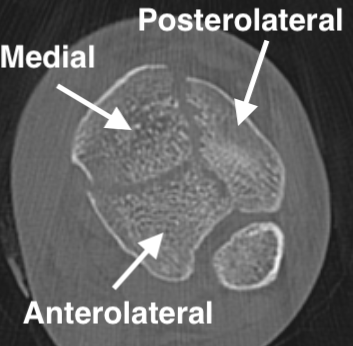

Commonly 3 fracture configurations

- medial malleolus

- posterolateral fragment / Volkmann

- anterolateral fragment / Chaput

Tibial plafond common fragmentsTibial plafond fragments